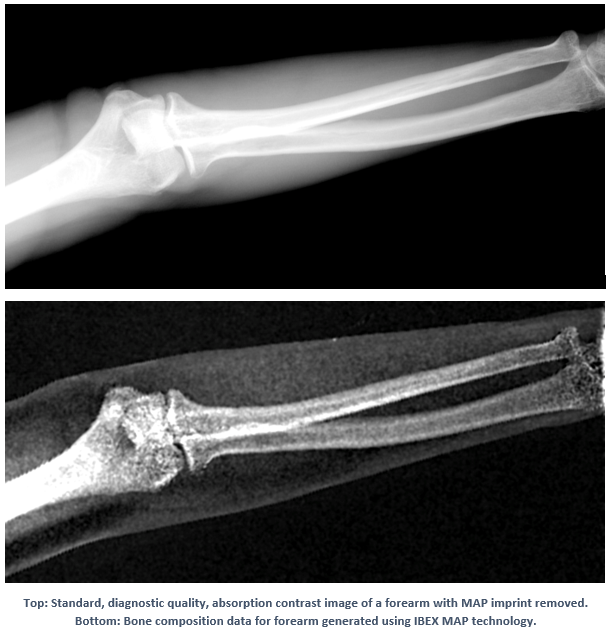

Comparison between standard absorption image and bone composition data collected using IBEX MAP tech